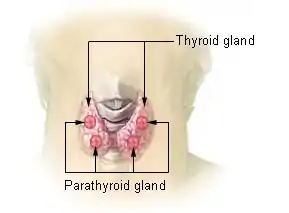

| Other names: Parathyroid hormone deficiency[1] | |

| Location of the four parathyroid glands | |

The parathyroid glands are so named because they are usually located behind the thyroid gland in the neck. They arise during fetal development from structures known as the third and fourth pharyngeal pouch. The glands, usually four in number, contain the parathyroid chief cells that sense the level of calcium in the blood through the calcium-sensing receptor and secrete parathyroid hormone. Magnesium is required for PTH secretion. Under normal circumstances, the parathyroids secrete PTH to maintain a calcium level within normal limits, as calcium is required for adequate muscle and nerve function (including the autonomic nervous system). PTH acts on several organs to increase calcium levels. It increases calcium absorption in the bowel, while in the kidney it prevents calcium excretion and increases phosphate release and in bone it increases calcium through bone resorption.